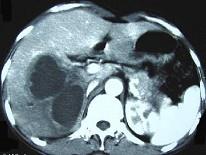

问题 男,45岁,右上腹痛,有发热,白细胞计数升高,CT检查如图,最可能诊断是 ( )

选项 A、肝黄色肉芽肿 B、肝转移癌 C、肝包虫病 D、肝脓肿 E、原发性肝癌

答案 D